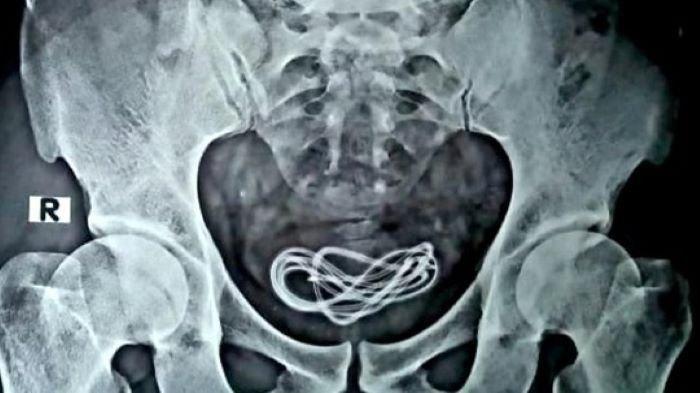

Dokter yang memeriksa Islam terkejut melihat apa yang ditemukannya. Di dalam kandung kemih Islam, terdapat kabel timah. Seorang dokter yang turut menangani mengaku, dirinya tidak pernah melihat hal seperti itu dalam 25 tahun karirnya.

Betapa tidak, dokter terkejut begitu menemukan kabel timah sepanjang 61 centimeter (cm) di dalam kandung kemih pria bernama Islam tersebut.

Dokter pun melakukan pemindaian sinar-X pada tubuh Islam.

Tak disangka, terdapat sesuatu di dalam kandung kemihnya.

Dalam hasil pemindaian sinar-X, untaian panjang melingkar di dalam kandung kemih.